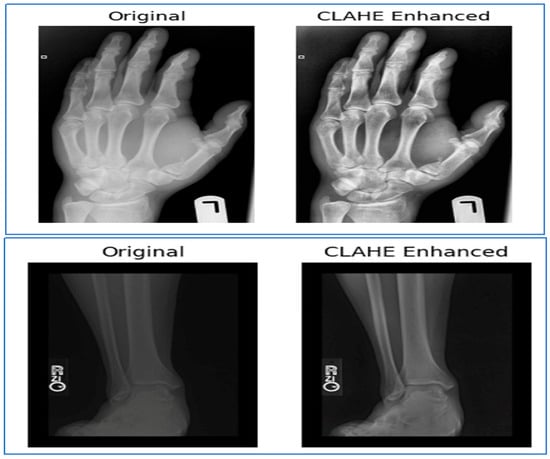

• Contrast Enhancement: Image contrast was enhanced to reduce sensitivity to lighting variations in radiographic scans and to improve the visibility of subtle fracture patterns. Figure 7 shows the images before and after contrast enhancement.

These preprocessing procedures ensured consistency across the dataset and prepared the input images for effective training and accurate BF classification.